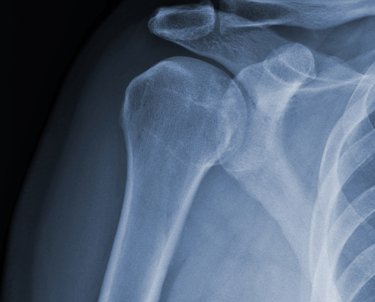

Evaluamos y tratamos lesiones que afectan los huesos, músculos, ligamentos y tendones. Desde fracturas y luxaciones hasta lesiones de tejidos blandos, ofrecemos un manejo médico y quirúrgico adecuado para una recuperación óptima.

Cirugías Ortopédicas Avanzadas.

Realizamos procedimientos quirúrgicos especializados, como:

Artroscopia: Técnica mínimamente invasiva utilizada para diagnosticar y tratar lesiones articulares, como desgarros de meniscos, lesiones de ligamentos y problemas en el cartílago.

Reemplazos articulares (prótesis de cadera, rodilla y hombro).